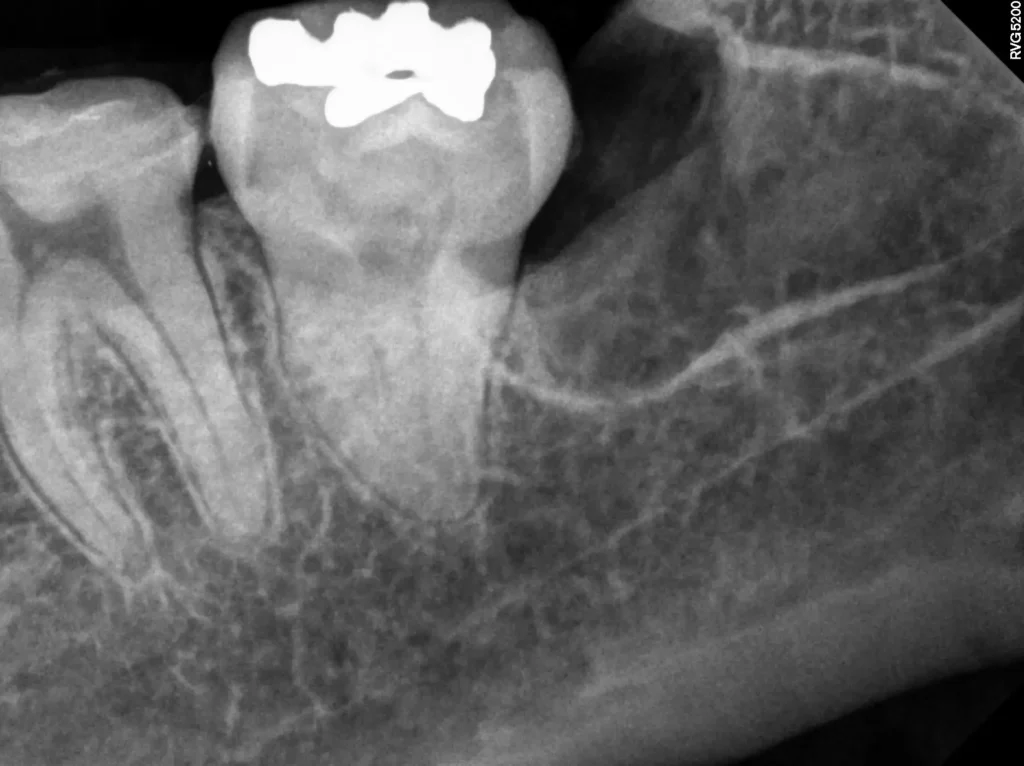

안 아픈 사랑니 (오른쪽 아래)

반대편에는 당장 아프지 않은 매복 사랑니가 있었습니다. 하지만 아프지 않다고 방치하면 다음과 같은 문제가 생길 수 있습니다.

- 치관주위염: 치아의 법랑질 주변의 치아 낭은 빈공간으로 입안과 개통될 경우 잠재적 오염 대상으로, 언제든 세균 감염이나 물혹을 유발할 수 있습니다.

- 인접 치아 손상: 바로 앞의 소중한 제2대구치(큰 어금니)에 충치를 만들거나 잇몸 질환을 일으킬 수 있습니다.

결국 환자분은 현재 아픈 사랑니뿐만 아니라, 잠재적 위험이 있는 반대편 매복 사랑니까지 모두 발치하기로 결정했습니다.